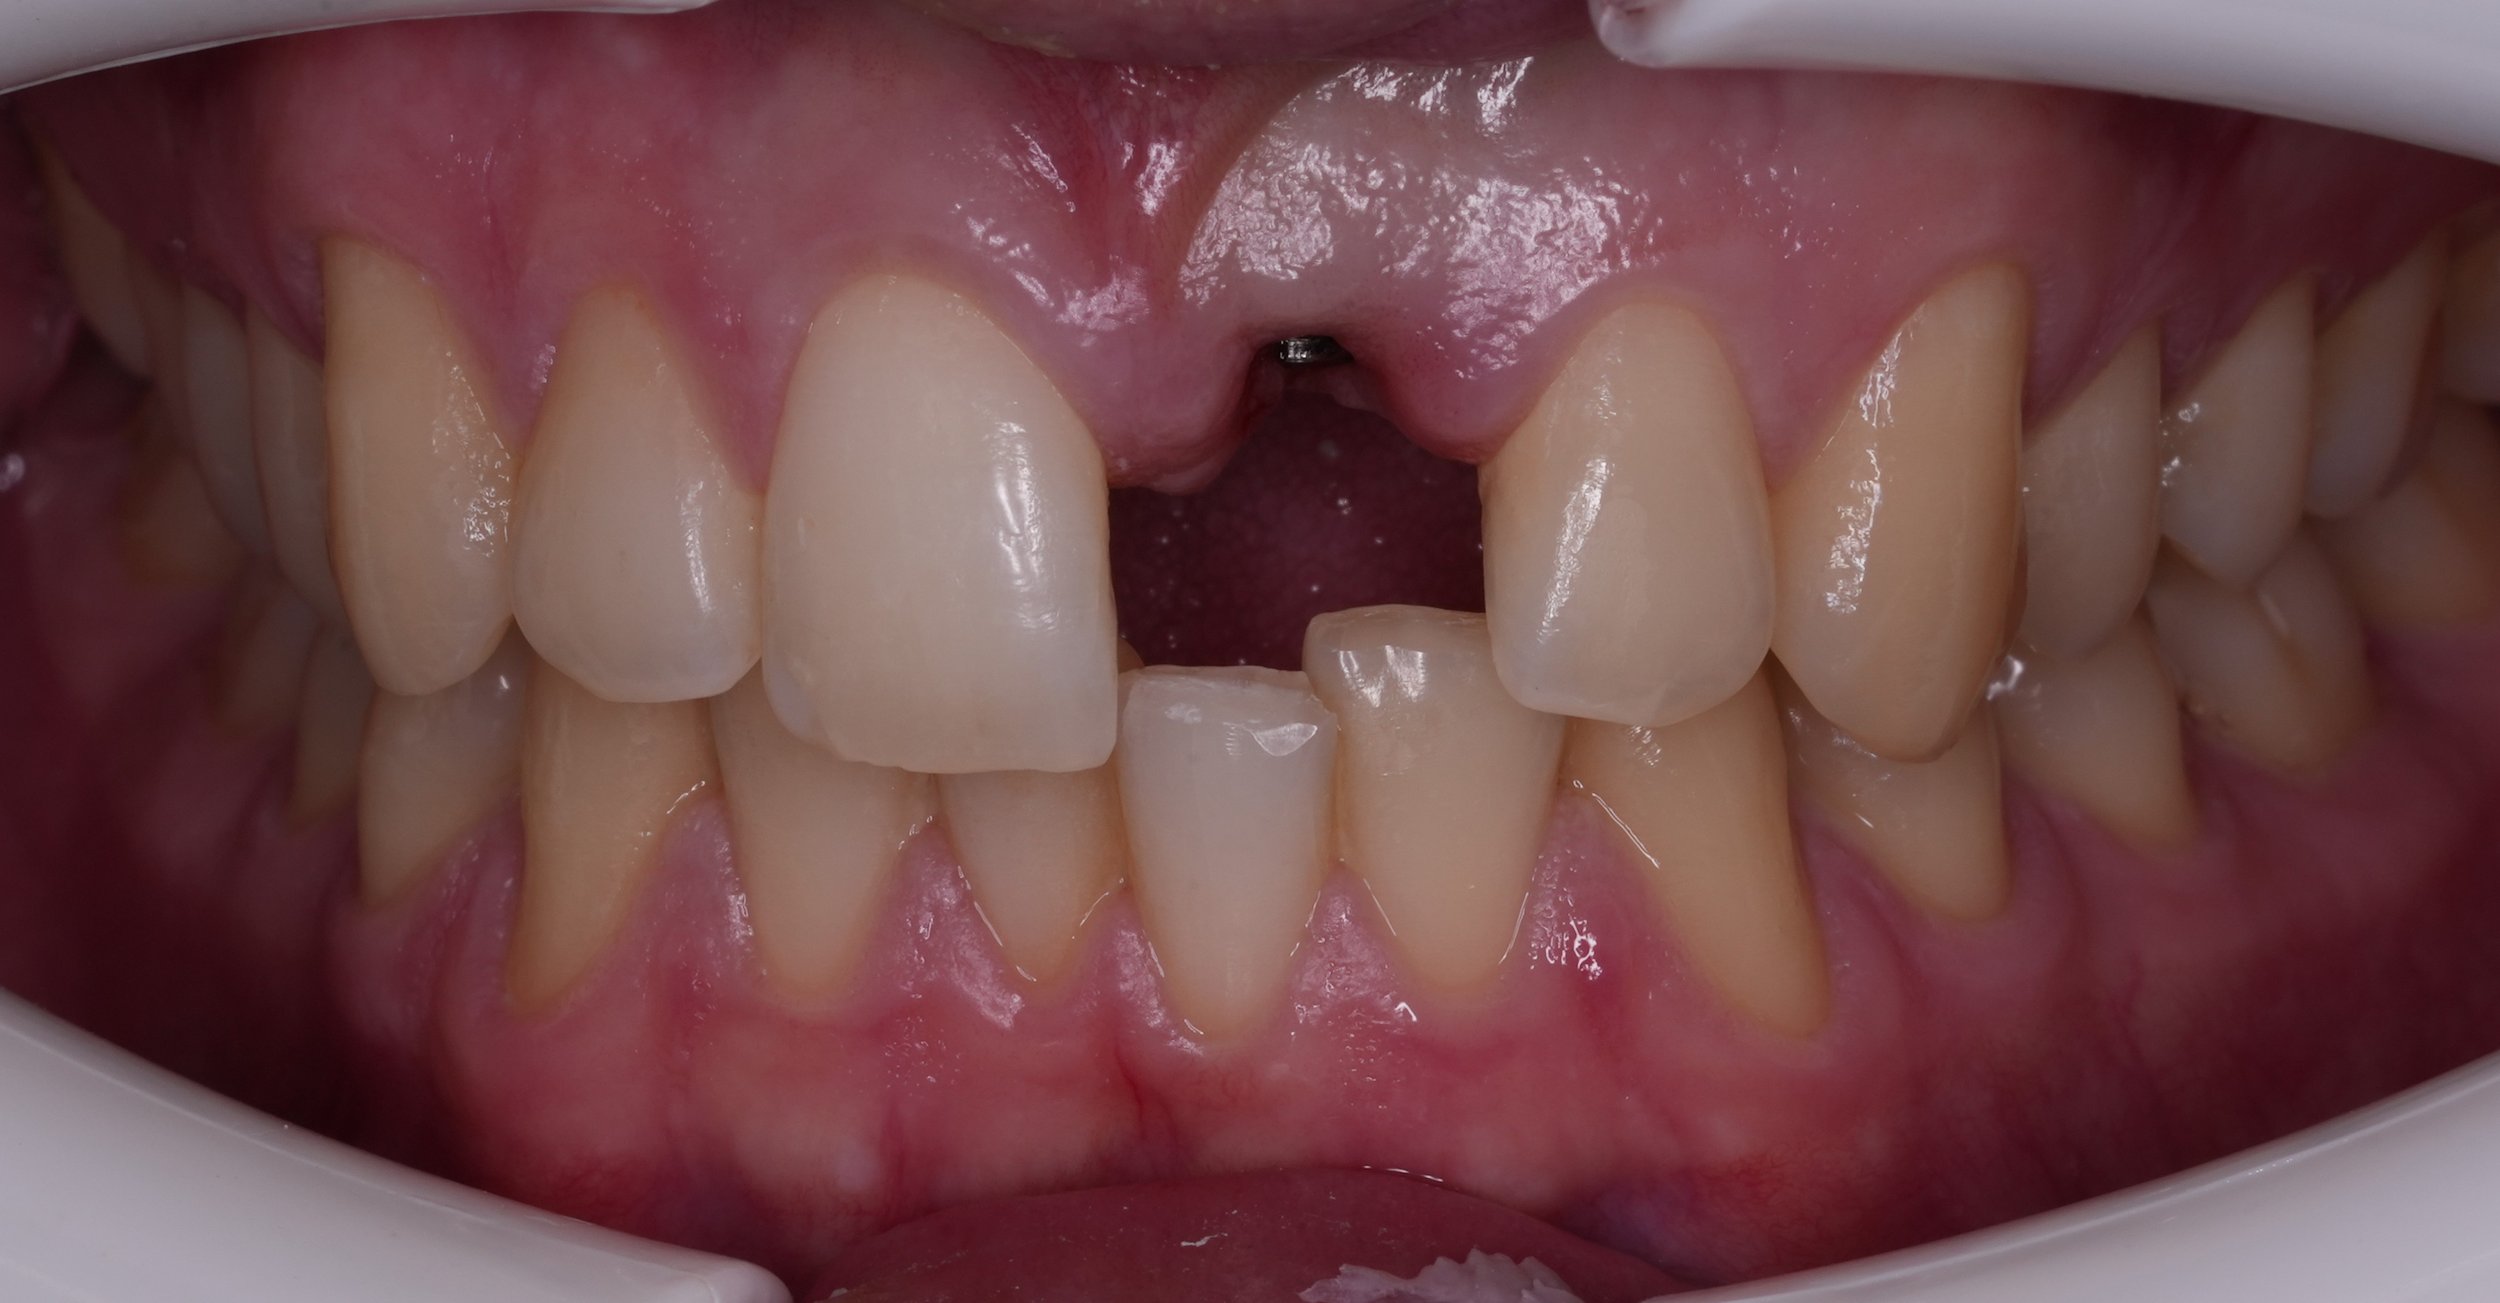

Fixed pros

Dental Implants